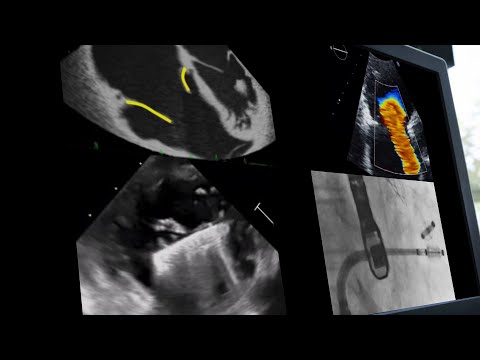

Echocardiographic imaging for transcatheter tricuspid intervention - Webinar

Transformative imaging in the clinical pathway of transcatheter tricuspid valve interventions

Imaging the journey of a patient with severe tricuspid regurgitation - Webinar

How to image patients referred for tricuspid regurgitation transcatheter interventions - Webinar

A systematic echo approach to the tricuspid valve: key for intervention

Whiteboard Lecture: Transcatheter Tricuspid Valve Interventions Procedural Imaging Correlation